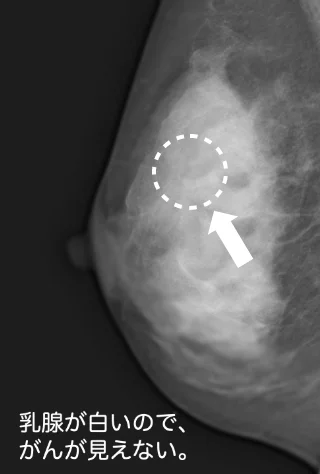

マンモグラフィの概要

マンモグラフィは乳房を圧迫して撮影するX線検査で、微細な石灰化や小さな腫瘍を発見するのに有効です。撮影は通常2方向から行われ、検査時間は数分程度です。圧迫による不快感や痛みが出ることもありますが、がんの早期発見には非常に効果的です。

マンモグラフィと超音波検査では、日本乳癌学会が発表する「乳癌診療ガイドライン」によって乳腺の発達の程度で有効性が変わると記載があります。どちらが良いかは自分で判断するのではなく必ず専門家に話を聞き選択してください。なお自治体等の集団検診では原則40歳以上の乳腺の減少した方を一斉に対象としているためマンモグラフィになります。